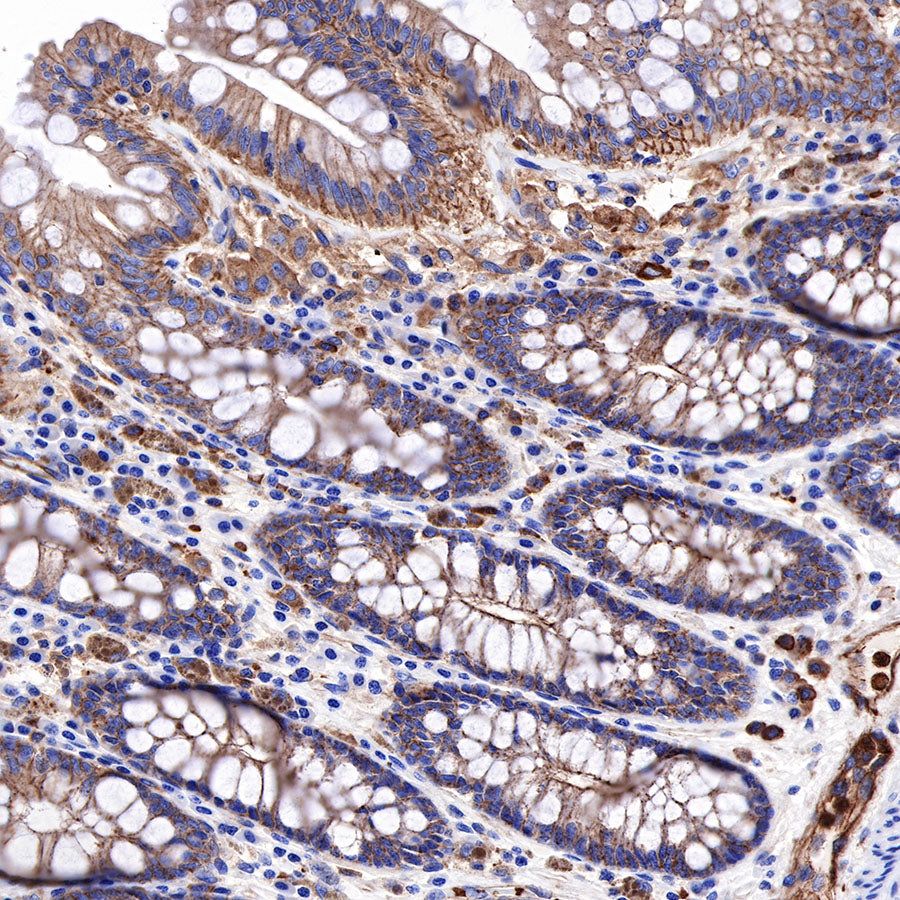

IHC shows positive staining in paraffin-embedded human colon. Anti-α-Actinin-1 antibody was used at 1/2000 dilution, followed by a HRP Polymer for Mouse & Rabbit IgG (ready to use). Counterstained with hematoxylin. Heat mediated antigen retrieval with Tris/EDTA buffer pH9.0 was performed before commencing with IHC staining protocol.